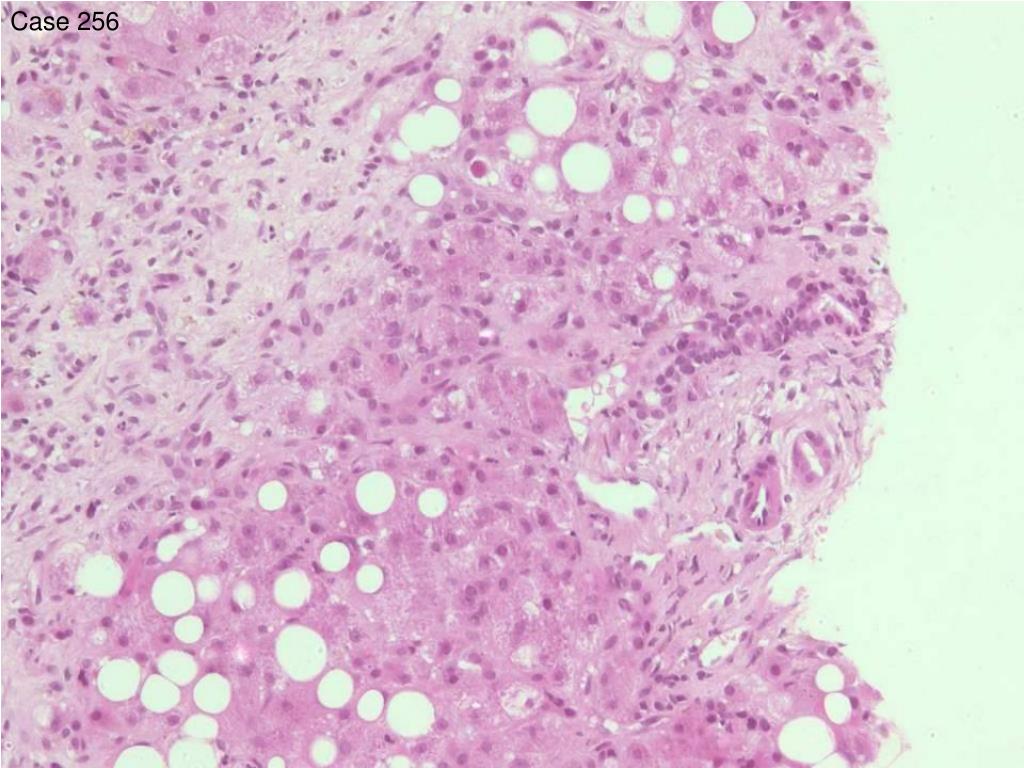

26. Case 256 • 57 F • Weight loss and jaundice. Positive SMA. ? autoimmune hepatitis. Bili 20, ALP 199, AST 243, Glob 32, SMA +ve

34. Case 256 • 37 steatohepatitis + fibrosis/cirrhosis, ? alcohol, not histological features of AIH • 19 steatohepatitis + fibrosis/cirrhosis, ? alchohol, no mention of AIH • 1 steatohepatitis rather than AIH, no mention of cause/alcohol • 1 steatohepatitis, PBC not excluded, no mention of AIH • 1 steatohepatitis with submassive necrosis or cirrhosis ? cause not diagnostic of AIH • 1 severe chronic hepatitis + cirrhosis, likely autoimmune • 1 hepatitic + biliary features, may be a variant syndrome

35. Case 256 • Scoring: Reject answers with no mention of steatohepatitis. • Responses with no mention of AIH score 5 • Discussion: Correct answers identified the diagnosis of steatohepatitis, and commented on the likely cause – in this case the marked degree of Mallory bodies and pericellular fibrosis makes alcohol extremely likely – these features of ‘central sclerosing hyaline necrosis’ are not seen to this degree in NASH. • Responses should include reference to the absence of histological features of autoimmune hepatitis, despite presence of smooth muscle antibodies – this was the clinical suspicion prompting the biopsy. Smooth muscle antibodies, like anti nuclear antibodies, are not uncommon in patients with alcoholic liver disease.

36. Case 256 • Original diagnosis: steatohepatitis with cirrhosis • Subsequent history of alcohol abuse obtained.